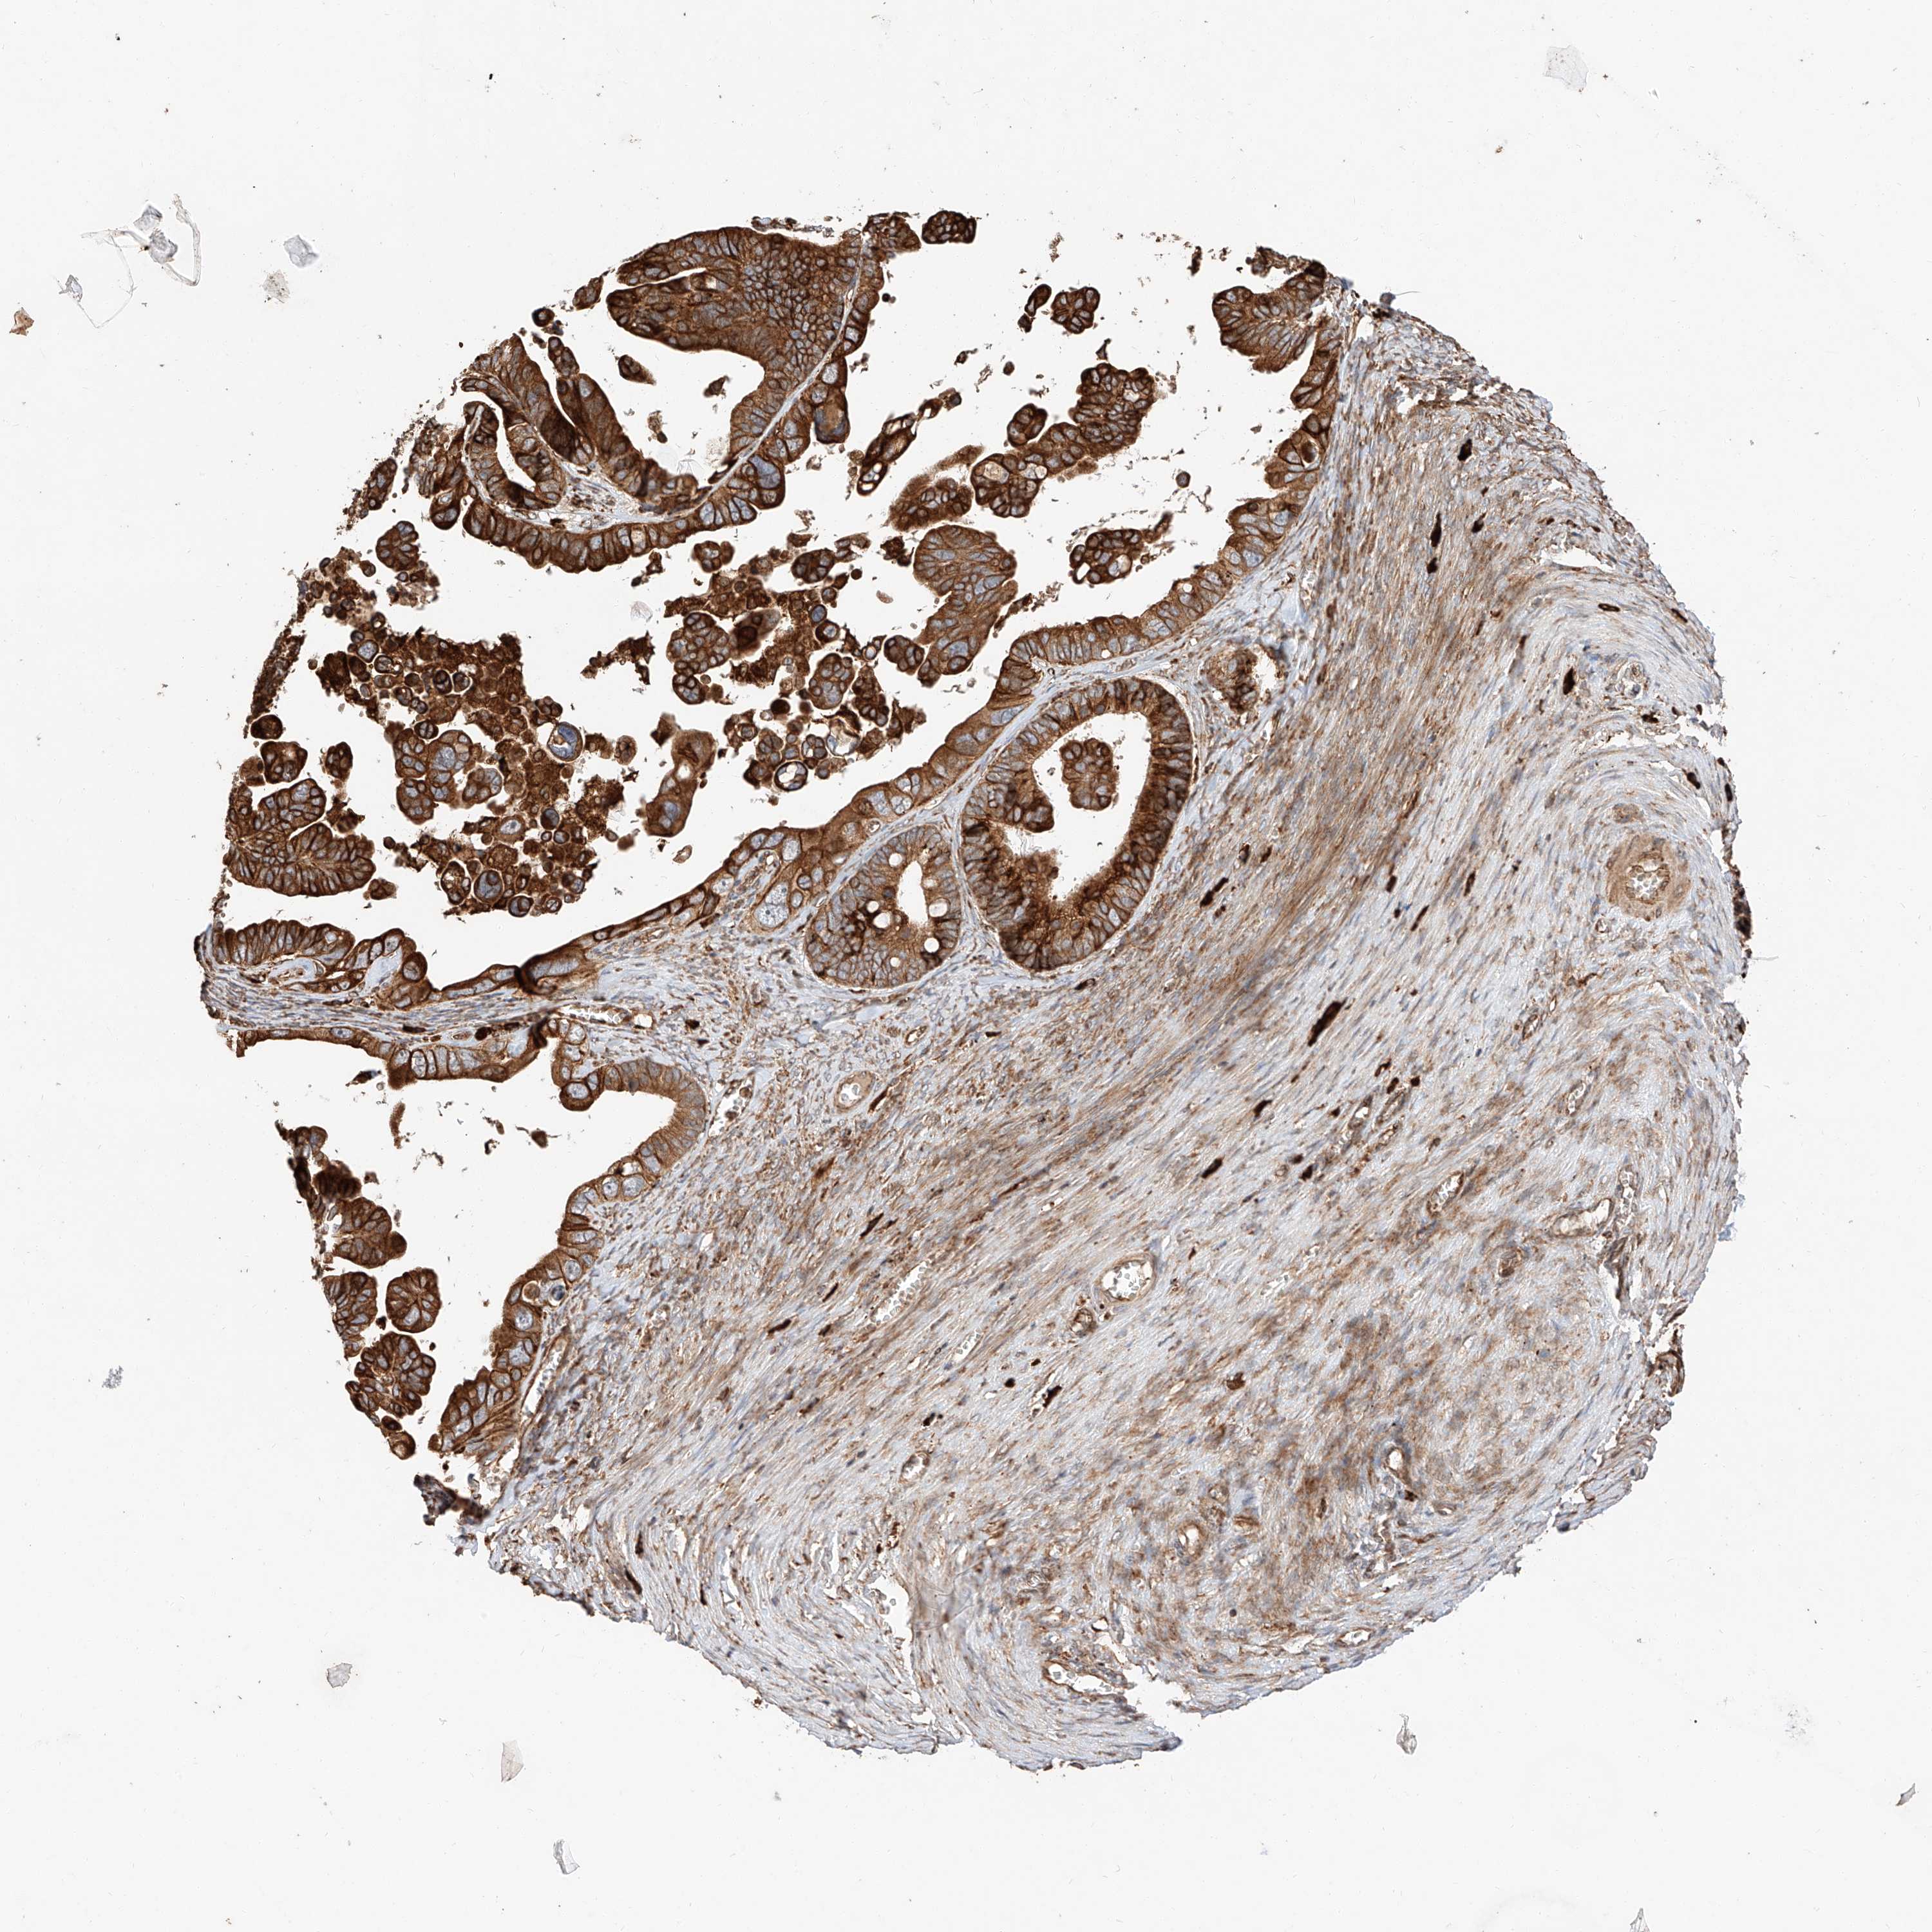

OVARIAN CANCER - Protein expressioni

A mouse-over function shows sample information and annotation data. Click on an image to view it in a full screen mode. Samples can be filtered based on level of antibody staining by selecting one or several of the following categories: high, medium, low and not detected. The assay and annotation is described here.

Note that samples used for immunohistochemistry by the Human Protein Atlas do not correspond to samples in the TCGA dataset.

Antibody stainingi

Antibody staining in the annotated cell types in the current human tissue is reported as not detected, low, medium, or high, based on conventional immunohistochemistry profiling in selected tissues. This score is based on the combination of the staining intensity and fraction of stained cells.

Each image is clickable and will lead to virtual microscopy that enables deeper exploration of all samples and also displays staining intensity scores, fraction scores and subcellular localization as well as patient and tissue information for each sample.

Antibody HPA028860

Staining

High

Medium

Low

Not detected

Intensity

Strong

Moderate

Weak

Negative

Quantity

>75%

75%-25%

<25%

None

Location

Nuclear

Cytoplasmic/membranous

Cytoplasmic/membranous,nuclear

Cystadenocarcinoma, serous, NOS

Carcinoma, endometroid

Cystadenocarcinoma, mucinous, NOS

Carcinoma, NOS